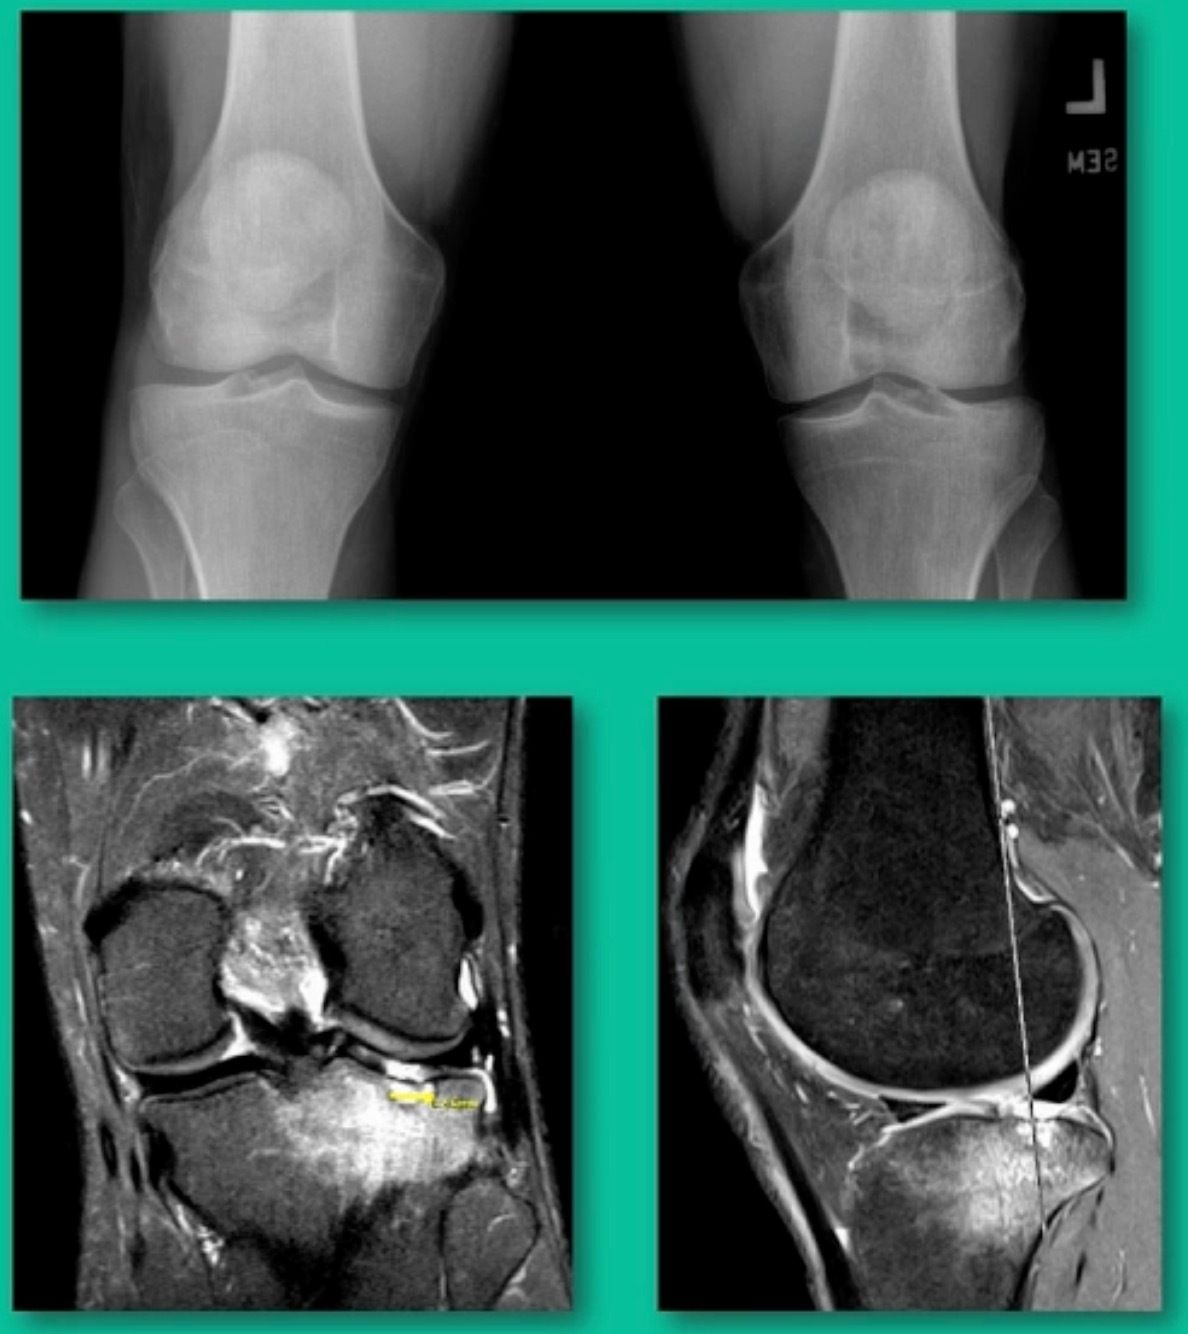

This is an 11-year-old. Left knee lateral knee pain. Effusions, the same type of classic findings (Figure 3)

You look at this one, you say, “what are you going to see when you get in there?” This is one when you get in there, you say, I’m not even sure I’m in the right knee because you almost don’t see it. That happens in patients who were painful, but they don’t look macroscopically unstable. Pediatric orthopedic surgeons tend to drill these. These are the ones that I see as failures. I think when you’re talking about something that’s mechanically unstable, it’s hard to understand why drilling would actually make it work without fixation. Even if it’s microscopically unstable.